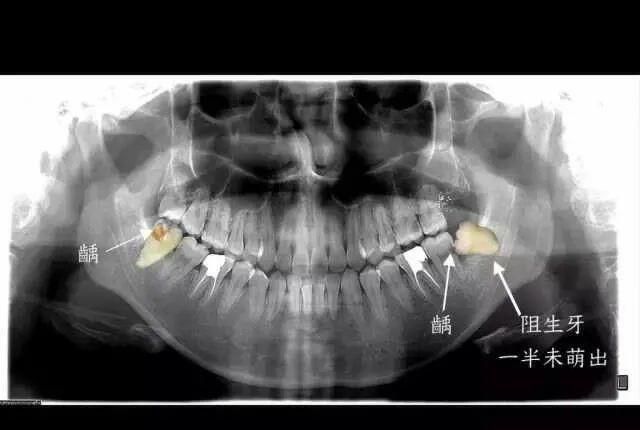

原因就在于长歪的智齿非常不容易清洁,食物常常会残留,有的就会导致智齿及周围组织疼痛,更严重的是,它还会导致智齿前方的磨牙出现蛀牙,进一步则出现牙痛,最严重的、也非常常见的状况是,智齿要拔掉先不说,连同智齿前方的第二磨牙都出现不可挽救的龋坏,只能一起拔掉。

△智齿前方的牙齿已经出现了蛀洞,即龋病。